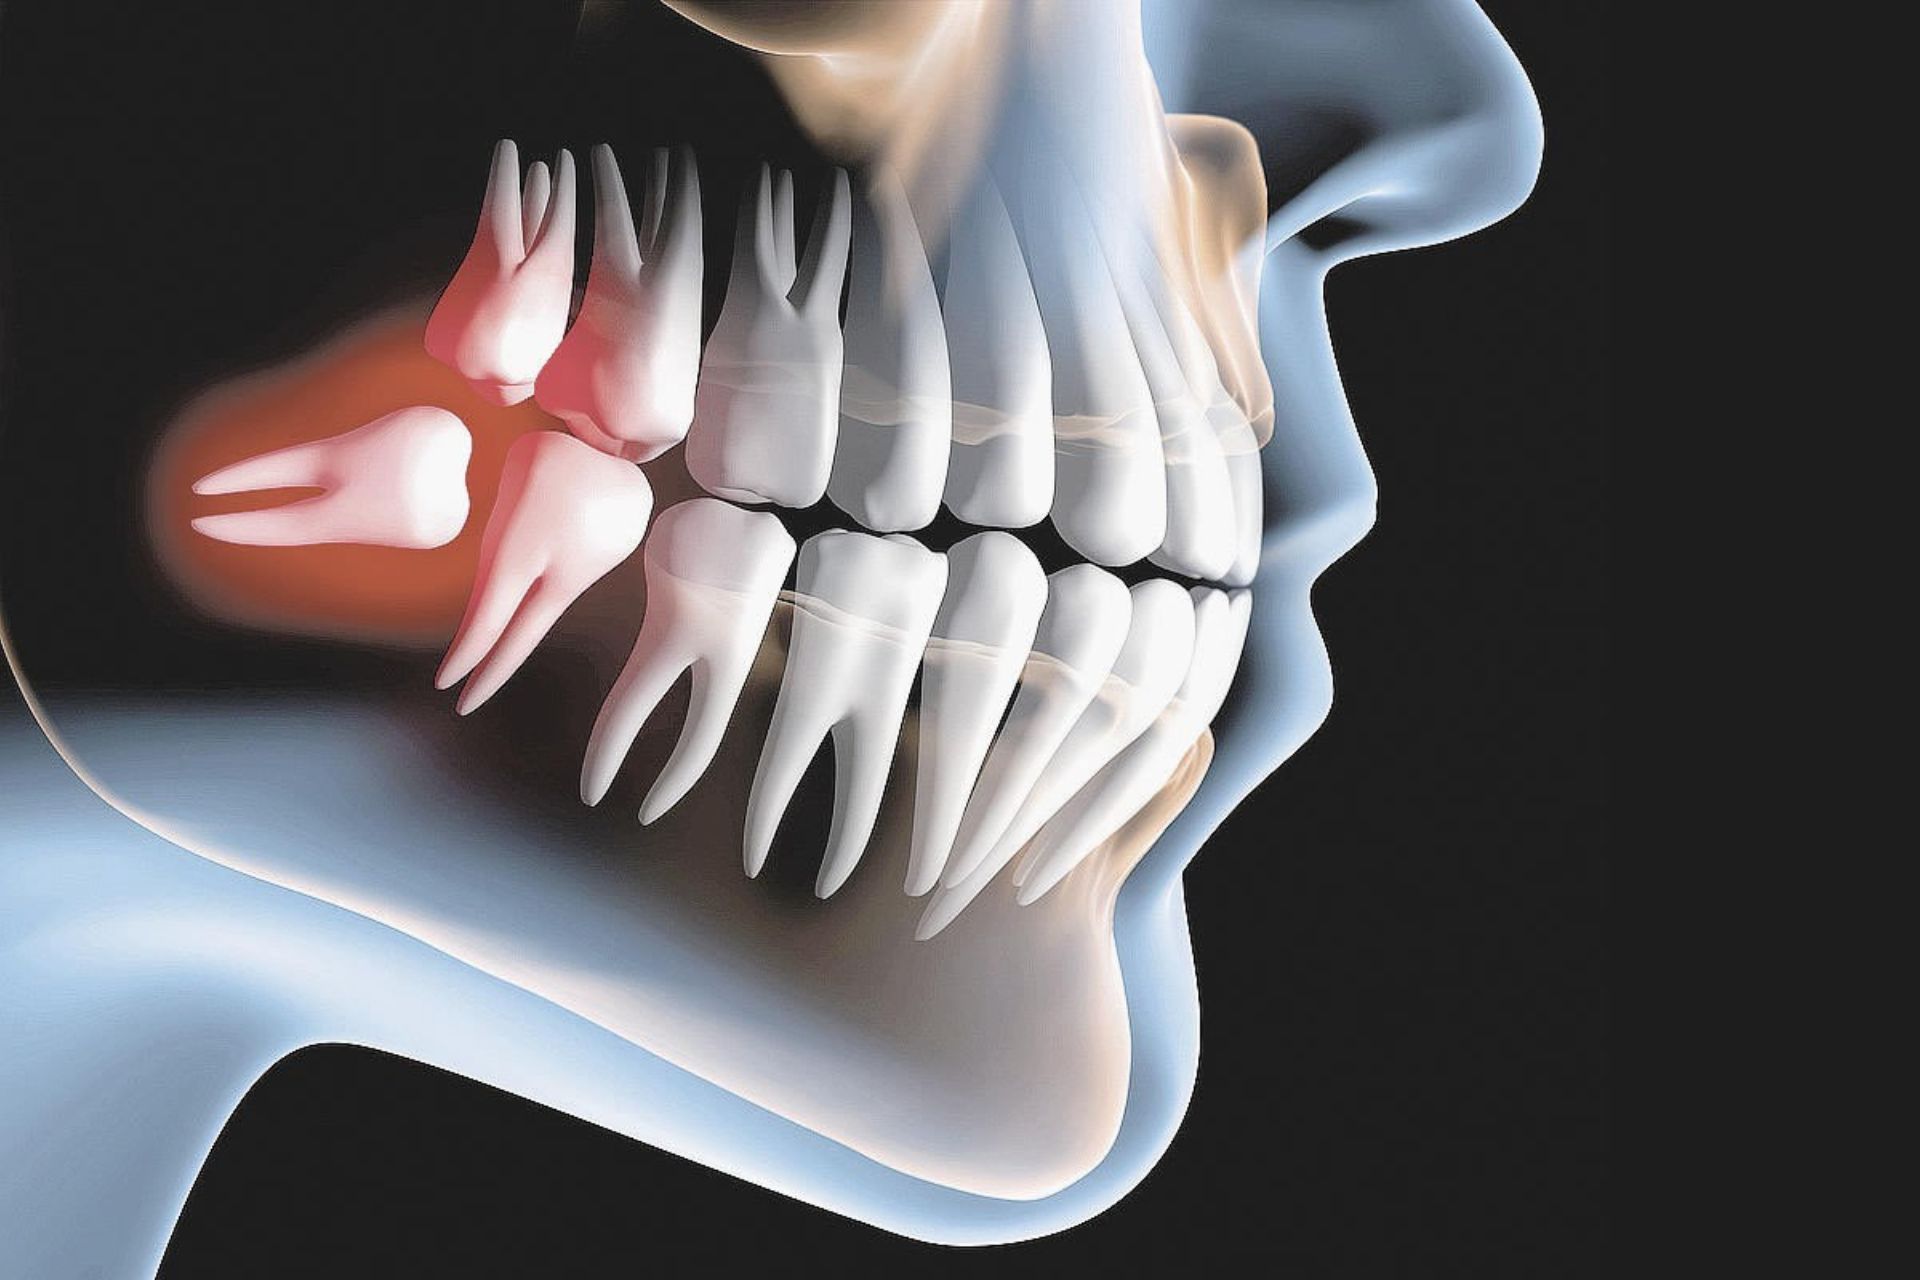

Esses quatro dentes extras, que formam o terceiro conjunto de molares, lá no final da mandíbula, contêm um centro de tecido mole chamado polpa dentária, que mantém o dente vivo.

Quase todos os humanos nascem com dentes do siso, porém, eles são frequentemente extraídos a partir da adolescência, quando pouco dano ao DNA ocorreu dentro da polpa dentária, tornando-os excepcionalmente maleáveis e mais seguros.